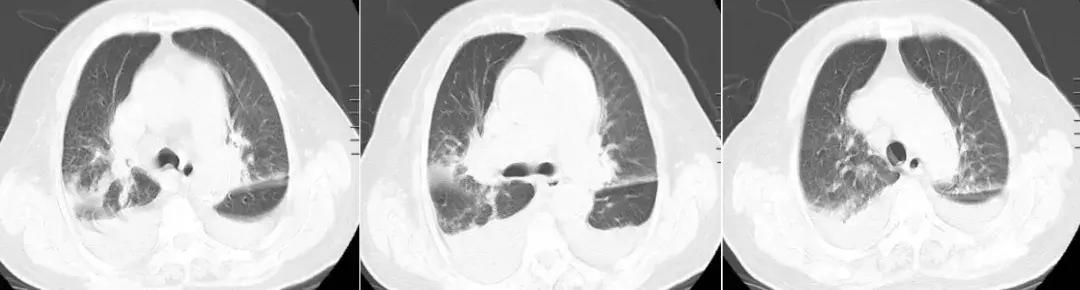

患者治疗陷入僵局,为明确呼吸困难原因,于入科第14天,行床旁心肺功能试验,同时复查肺部CT。结果提示运动心功能明显异常(见图2);肺CT(见图3)见右肺上叶、中叶改变较前无明显变化,炎症吸收好转,双侧胸腔积液。复查心脏彩超仍提示舒张功能减低,射血分数正常。

【图3】复查胸部CT:右肺上叶、中叶支气管改变,炎症吸收好转,双侧胸腔积液。